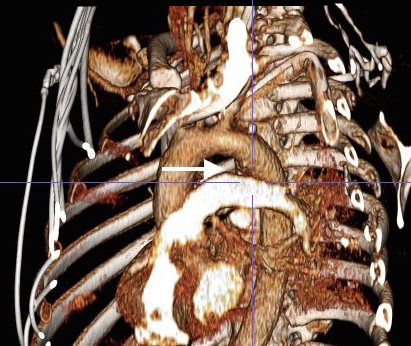

This patient presents with lifestyle limiting claudication and an absent right femoral pulse. ABI is moderately reduced on the right to 0.57, and he had no rest pain. CTA at our clinic revealed an occluded EIA bracketed by severely calcified and nearly occlusive plaque of the common iliac artery (CIA) and common femoral artery (CFA).

The patient was amenable to operation. Traditionally, this would have been treated with some form of bypass -aortofemoral or femorofemoral with a common femoral endarterectomy. While endovascular therapy of the occluded segment is available, one should not expect the patencies to be any better than that of occlusive lesions (CTO’s) in other arteries. Hybrid open/endovascular therapy is an option as well with CFA endarterecotmy and crossing CIA to EIA stents, but I have a better solution.